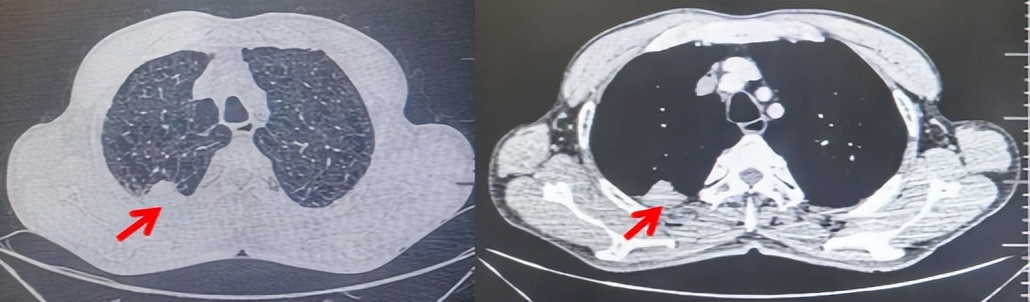

2024.11.19患者出现右侧胸痛,复查胸部CT检查示右侧胸膜肿物,大小约31mmX24mm,右侧4、5肋骨骨质破坏,考虑转移(如图2)。建议患者穿刺活检取病理明确诊断,患者拒绝,经MDT会诊后结合影像学表现及病史考虑为胸膜转移,肋骨转移,分期为rT0N0M1a IVA期,DFS仅仅17个月。2024.12.05起行信迪利单抗联合培美曲塞+卡铂方案治疗4周期,复查胸CT评效PR(如图3)。之后给予信迪利单抗+培美曲塞维持治疗6周期,期间复查CT评效PR(如图3)。目前信迪利单抗+培美曲塞维持治疗中,截止至目前PFS约为8个月,治疗期间未出现明显毒副反应。

图3:患者免疫联合化疗治疗后胸部CT,(A、B)图展示信迪利单抗联合培美曲塞+卡铂治疗

4周期(2025.02)疗效,(C、D)图展示信迪利单抗+培美曲塞维持治疗6周期(2025.07)疗效